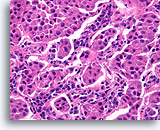

Invasief Ductaal carcinoom, Borst FNA, Celblok.

Eén residuele, vermoedelijk niet-invasieve melkgang kan worden waargenomen uiterst rechtsboven in de afbeelding (open pijl). Invasiviteit kan worden gediagnosticeerd in de andere onregelmatige, solide, dunne clusters met maligne ductale cellen die het geactiveerde stromaweefsel willekeurig doorsnijden (pijlen).

Invasief Ductaal carcinoom, Borst FNA, Celblok.

Eén residuele, vermoedelijk niet-invasieve melkgang kan worden waargenomen uiterst rechtsboven in de afbeelding (open pijl). Invasiviteit kan worden gediagnosticeerd in de andere onregelmatige, solide, dunne clusters met maligne ductale cellen die het geactiveerde stromaweefsel willekeurig doorsnijden (pijlen).

Invasief Ductaal carcinoom, Borst FNA, Celblok.

In dit gebied infiltreren borstkankercellen (pijlen) in enkele natieve melkgangen (open pijlen).

Invasief Ductaal carcinoom, Borst FNA, Celblok.

In dit gebied infiltreren borstkankercellen (pijlen) in enkele natieve melkgangen (open pijlen).